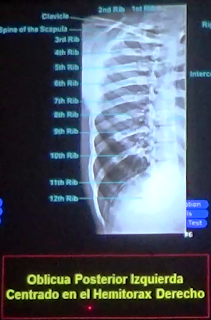

PARRILLA COSTAL

Para el estudio de la parrilla costal se hace uso

de las proyecciones

-frontal

-oblicua

-lateral

PROYECCIÓN FRONTAL DE PARRILLA COSTAL

Esta proyección nos permite ver panorámicamente los arcos costales de la

jaula torácica. En esta proyección se presenta la superposición de costillas a

nivel del ángulo costal.

Los arcos costales tienen una disposición oblicua y

hacia debajo de posterior a anterior. En la imagen de arriba observamos

claramente la superposición de los cuerpos costales debido a la forma oblicua

en que descienden los arcos costales anteriores sobre los posteriores.

En la imagen de abajo observamos la situación de

las escapulas y los espacios intercostales, que normalmente deben ser

simétricos en ambos hemitorax. Observamos también como el primer arco costal se

superpone con el segundo, tercero y cuarto arco costal. Recordemos que el

tercio anterior del arco costal no se visualiza en la radiografía por ser

transparente a los rayos x (cartílago costal).

PROYECCION OBLICUA DE PARRILLA COSTAL

En esta proyección lo que se busca es estirar el

arco costal para verlo mejor

En principio debemos decir que existen dos

proyecciones oblicuas la anterior y la posterior.

La proyección oblicua posterior es la que se

practica normalmente en el radiodiagnóstico. La oblicua anterior no es

necesaria porque los arcos costales anteriores solo se visualizan hasta el

inicio de los cartílagos costales. Es mejor tomar las radiografías con los

arcos costales posteriores cerca del receptor de imagen.

En esta proyección los arcos costales posteriores

se observan en toda su extensión. Ya no se encuentran superpuestos con los

arcos costales anteriores como en la proyección frontal.

En la imagen de arriba observamos una proyección

lateral de parrilla costal. Es evidente la superposición de arcos costales de

ambos hemitorax.